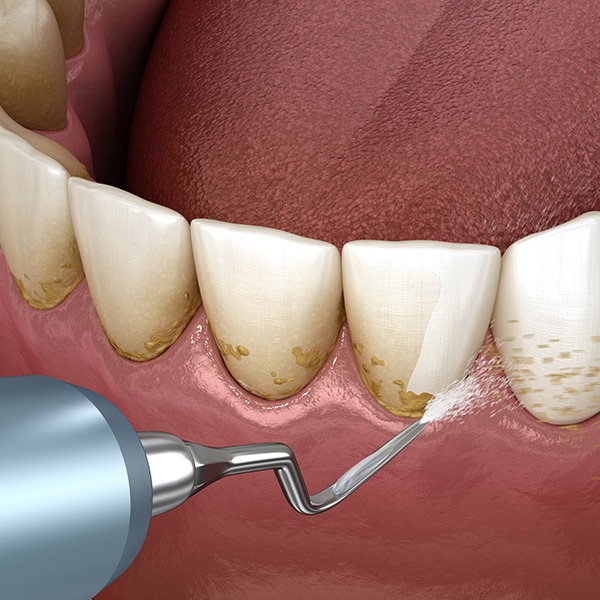

Read more/中文Periodontics

Keep your gums in top shape!

Periodontics takes care of your gums and the supporting structures of your teeth. It's like the bodyguard for your teeth, making sure they stay healthy and stable in your mouth.

EMS Piezon Airflow

Most effective when used in periodontal therapy, implant maintenance, and stain removal and with minimal discomfort compared to traditional methods.